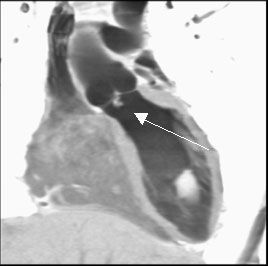

3. острые коронарные синдромы, инфаркты миокарда без подъема ST для оценки поражения венечных артерий сердца [16]. МСКТ позволяет диагностировать возможные осложнения при инфаркте миокарда, к примеру, разрыв межжелудочковой перегородки (рис № 2) [56], а так же развитие аневризмы левого желудочка (рис № 3).

![]() |

| Рис.2. МСКТ сердца. Аневризма в области верхушки левого желудочка (стрелка), кальциноз коронарных артерий. |

| Рис.3. МСКТ сердца. Разрыв межжелудочковой перегородки при остром инфаркте миокарда (стрелка). |